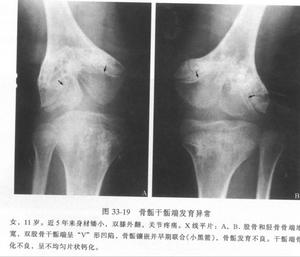

初生並無不良,股骨頭二次骨化中心出現延遲往往是最早的x線徵象,可以延遲到1—2歲才出現。股骨頭骺不規則,密度增加、不均勻、斑駁、破碎,很像Perthes病的表現。其他部位如股骨遠端,脛骨近端,脛骨遠端,肘、腕關節骨骺,均可有程度不等的變異,腕骨和跗骨間可發生融合。待發育成熟骨骺閉合後,關節面不規則,呈桑椹狀,股骨頸乾角減小,短頸、扁平髖,膝關節力線不良,內翻或外翻,踝關節踝穴變形,距骨滑車塌陷變扁,距骨頸變短,距骨頭扁平,距骨缺血壞死,跗骨扭曲,趾骨短縮,肘關節、腕關節間隙明顯變窄,尺撓骨發育不對稱,腕骨扭曲,掌骨變短。個別病例累及椎體,表現為椎體不規則,前方稍呈楔狀變形。

多發性骨骺發育不良--X片多發性骨骺發育不良是少見的先天性骨發育障礙,本病為常染色體顯性遺傳性骨病,現將1例多發性骨骺發育不良報告如下。

患者,男,10歲,全身關節痛5年余,近1年來,全身關節疼痛更顯著,活動後易疲勞。其家族無其他人患此病。查體:身高106cm,體重26kg,智力尚正常,步態不穩。“X”型腿,雙手粗而短,指間關節腫脹,雙肘、雙膝、雙踝粗大,無紅熱,脊柱後凸,四肢與軀幹基本均稱。實驗室檢查:無不良發現。X線表現:兩側骨骺對稱性受累,骨骺發育小及變扁,可見呈分節或斑點狀,邊緣不規則,但無硬化帶。雙手掌指骨短,乾骺端粗大,雙舟骨不規則狀變形,各腕骨間骨間隙變窄。脊柱各椎體稍變扁,上下緣不規則且毛糙,頸椎下各

椎間隙稍變窄,腰椎第3、4、5椎體前後徑小,且胸腰段以胸11椎體至腰1椎體為中心後凸畸形。骨盆變窄,呈狹長型改變,雙股骨頭骨骺變扁平,並見有分節及斑點狀改變,股骨頸變短,髖臼變淺,雙膝關節間隙外寬內窄,雙側脛骨遠端骨骺外側部分發育不良,較細小,骨骺呈尖端指向外側之楔形,雙踝關節面傾斜。

多發性骨骺發育不良多發性骨骺發育不良據資料於1921年首先被Barringten-Ward報導,1947年命名。本病僅侵犯骨骺軟骨,主要為軟骨發育過程中先期鈣化帶區的軟骨細胞未成熟,數量減少、排列不規整,致骨化障礙。本病男女均可發病,約50%系家族性發病。一般於4歲以後出現症狀,表現為關節疼痛,運動障礙和步態不穩。病變只侵犯及骨骺,以兒童時期最顯著,尤其以11-12歲症狀最明顯,青春期後隨年齡增長症狀可改善。身材較短小,四肢與軀幹基本勻稱,手足可粗短。表現為骨骺發育小而且變扁,邊緣不規則,可呈分節或斑點狀,但無硬化。管狀骨變短,關節面傾斜,脊柱後凸畸形,脛骨遠端骨骺有特徵性表現。隨年齡增長而乾骺端變小、扁平及關節畸形,較早地引起退行性骨關節病。本病須與軟骨發育不全、乾骺發育不良等骨關節發育障礙相鑑別。如能結合病史及其特徵性X線表現,是不難鑑別的。